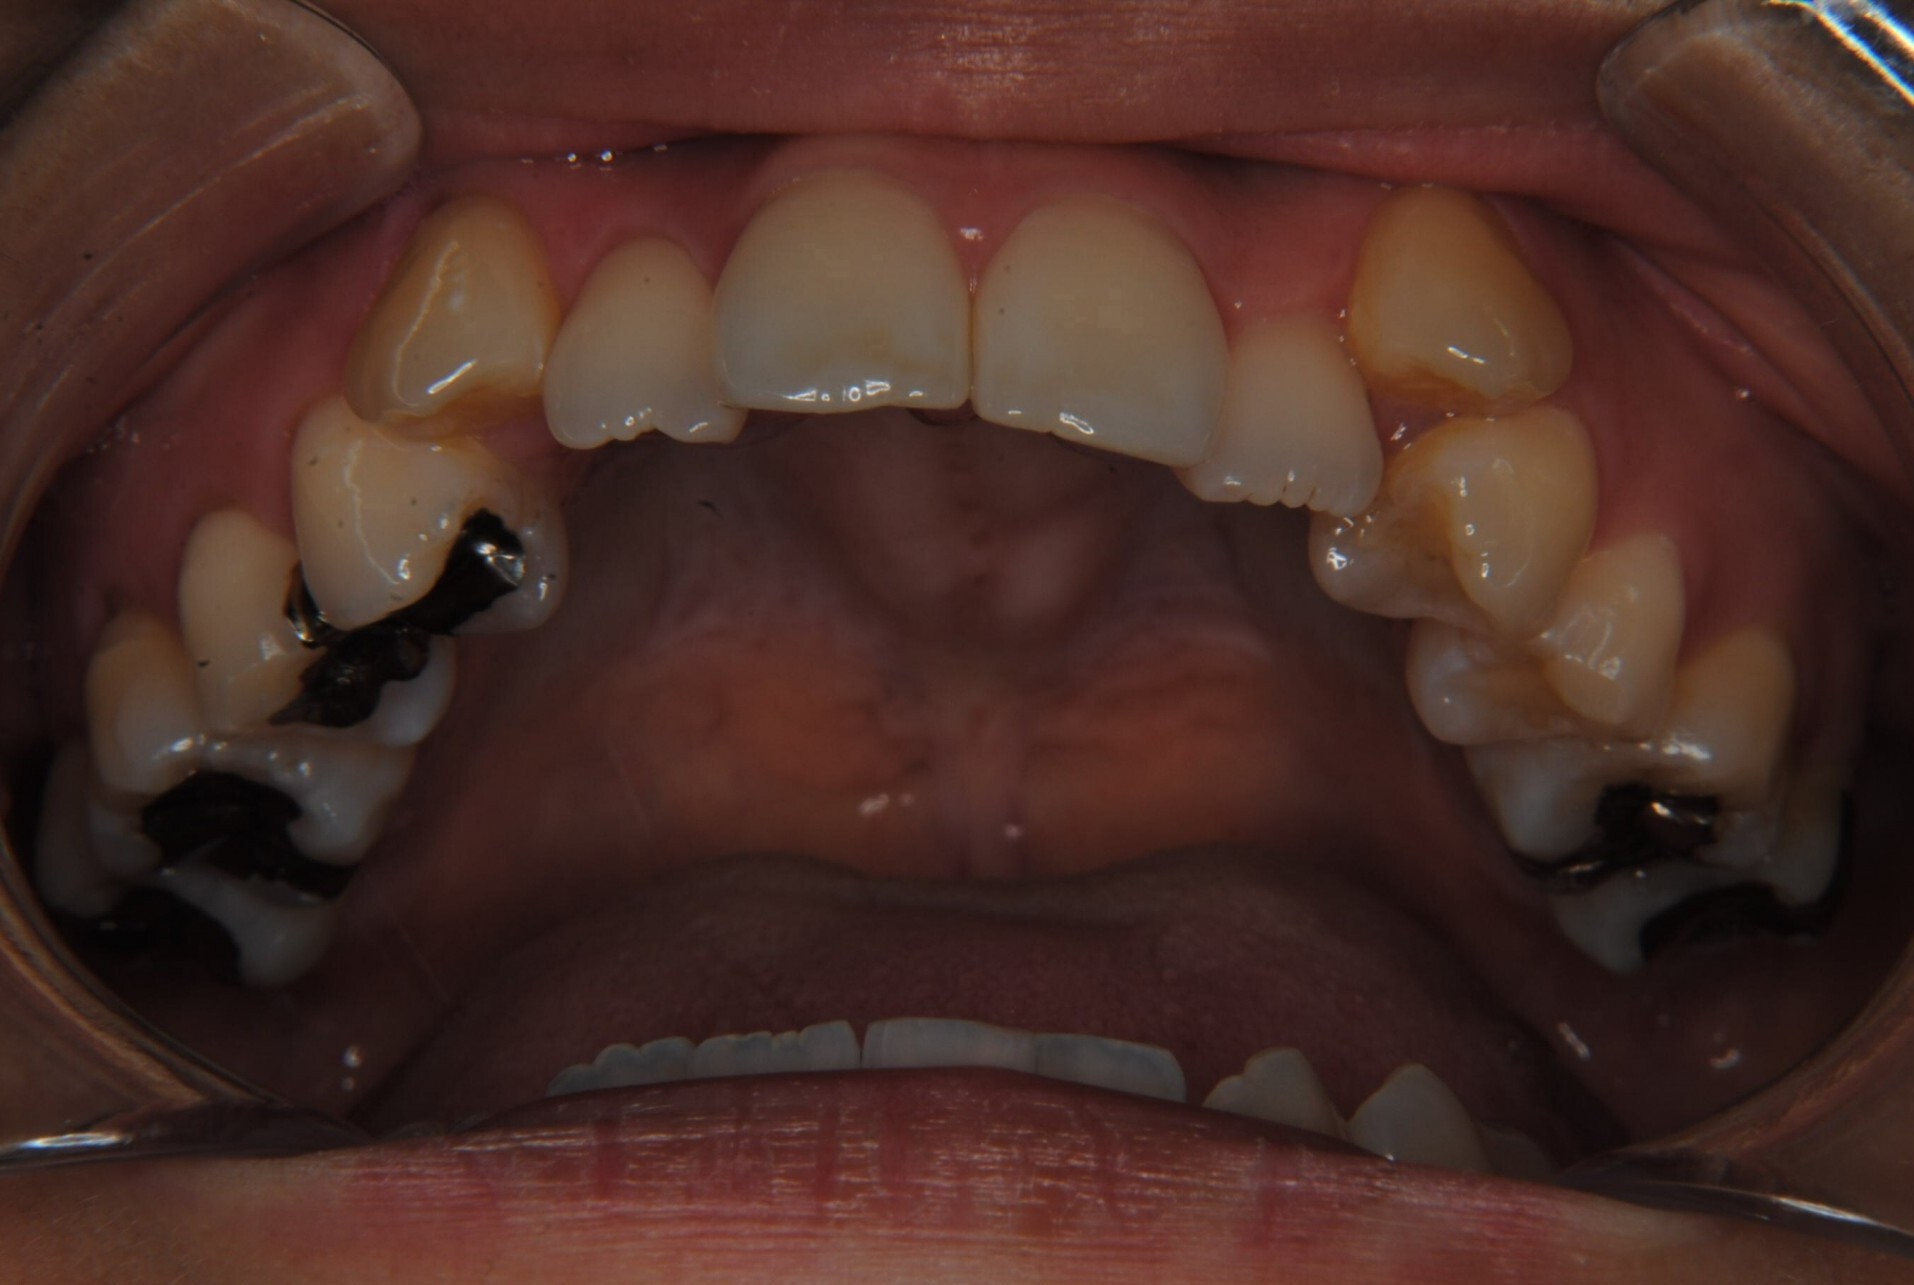

①主訴:八重歯、前歯のガタガタ、真ん中の不一致を治したい

②診断名:AngleⅠ級叢生

④治療に用いた主な装置:マルチブラケット装置(T21ブラケット)

⑤抜歯部位:上下左右第一小臼歯

⑧リスクと副作用:マルチブラケット装置(T21ブラケット)を初めてつけてから4日間、食事の時におもに前歯が少し痛かったとのことでした。治療後のエックス線写真で、歯根吸収はほとんど観察されず、歯肉を診ると残念ながら下顎前歯部に歯肉退縮(ブラックトライアングル)が生じていました。しかし、通常下顎前歯部は下唇に隠れてむき出しにはなっていないので、ご本人はあまり気にされていないご様子でホッとしています。